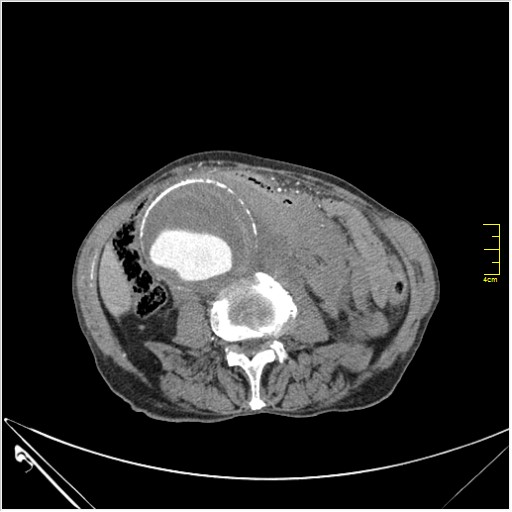

Пациент Т. 64 года, обратился на КТ брюшной полости амбулаторно (!), по направлению семейного врача с диагнозом abdominal mass, буквально: образование брюшной полости.

Huge abdominal aorta aneurism. Simple renal cortical cysts (Bosniak type 1).